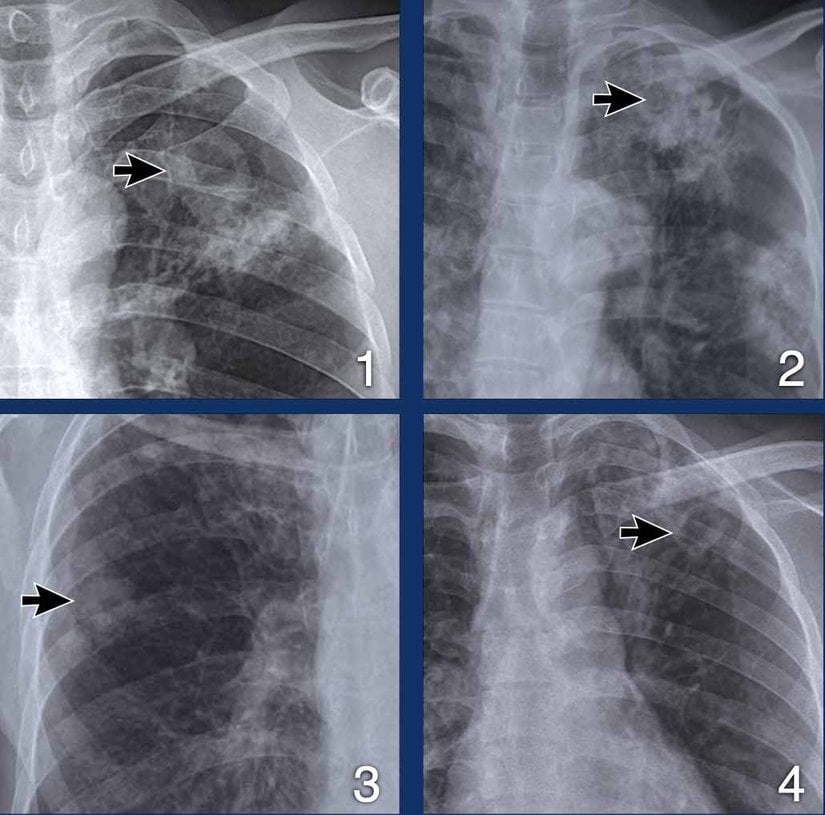

Tüberkülozun radyografik bulguları aşağıdakileri içerebilir:

- Akciğer tüberkülozu olan HIV-negatif kişilerin %60'ında ve akciğer tüberkülozu olan HIV-pozitif kişilerin %22'sinde göğüs röntgeni normal görünebilir veya belirgin bir bulgu saptanmayabilir.

- Göğüs röntgeni, nüfusun çoğunluğunda tüberküloz hastalığının tanı ve takibinin temel taşıdır. Üst lobun apikal veya subapikal posterior bölgelerinde veya alt lobun superior segmentlerinde sıklıkla yamalı veya nodüler bir infiltrat görülür.

- BT veya MR görüntülemede daha belirgin olan kavite oluşumu da görülebilir. Hava sıvısı seviyeleri daha çok alt lob boşluklarında görülür.

- Fibrotik skarlar keskin sınırlarla görülebilir.

- Alt lob tüberküloz bulguları nonspesifiktir ve kötü rezolüsyonlu pnömoni, atelektazi, kitle lezyonları ve kaviteleri içerir.

- Hiler lenfadenopati ile birlikte pnömoni primer tüberkülozun göstergesidir.

Düz akciğer grafiğinde kavitasyon bulunan tüberküloz hastalarının, yayma durumu dikkate alındıktan sonra, kavitasyon bulunmayan hastalara kıyasla daha enfeksiyöz (bulaşıcı) olduğu düşünülmektedir. Akciğer kavitasyonu olan yayma pozitif tüberküloz hastaları, kavitasyon olmayanlara göre daha yüksek yarı kantitatif yayma sonuçlarına sahiptir. Tipik göğüs radyografisi bulguları olan yayma pozitif tüberküloz hastaları, diğer tüm atipik göğüs radyografisi bulguları olan yayma pozitif tüberküloz hastalarından daha bulaşıcıdır.

Göğüs Radyografisi

Göğüs radyografisi, akciğer tüberkülozunu taramak için en yaygın kullanılan testler arasındadır. Erişilebilir olduğu yerlerde, ya tüberküloz tanısal değerlendirmesinin rutin bir parçası olarak ya da daha kısıtlı kaynaklara sahip ortamlarda, balgam üretemeyen veya balgamın hızlı mikrobiyolojik incelemesinde (örn. yayma mikroskopisi veya nükleik asit amplifikasyon testleri ile) negatif çıkan bireylerde bir takip testi olarak yapılır.

Göğüs radyografisinin şiddetle tavsiye edildiği diğer gruplar HIV ile yaşayan kişiler ve göğüs radyografisinin ek tanısal değerlendirmeyi (örneğin, plevral efüzyonu düşündüren fiziksel bulgular) veya yönetimi (örneğin, bronkoskopi veya başka bir müdahalenin endike olabileceği önemli hemoptizisi olan bir hasta) etkileyebileceği kişilerdir. Bireylerin ağırlıklı olarak asemptomatik ve klinik öncesi hastalığa sahip olduğu toplum ortamlarında aktif vaka bulma sırasında, akciğer grafisi tüberküloz tanılarının verimini önemli ölçüde artırabilir. Bu deneyim, bilgisayar destekli yorumlama özelliğine sahip, düşük maliyetli, taşınabilir dijital radyografiye olan ilgiyi artırmıştır.

Akciğer tüberkülozunun radyografik bulguları enfeksiyon ve hastalığın evrelerine bağlıdır. Primer enfeksiyon sırasında, granülom oluşumu parankimde fokal bir skar veya kalıcı nodüle (Ghon lezyonu olarak adlandırılır) ve bazen hilum ve/veya mediastende kalsifiye lenf düğümlerine yol açabilir ve bunlar birlikte görüldüğünde Ranke kompleksi olarak adlandırılır. Bireylerin önemli bir azınlığında, bu radyografik anormallikler kalsifikasyonlu veya kalsifikasyonsuz bir skar veya kalınlaşma olarak devam edecek ve tarama göğüs radyografisinde veya bilgisayarlı tomografide ömür boyu tespit edilebilecek klinik öneme sahip olacaktır.

Primer tüberküloz enfeksiyonunu kontrol altına alamayan bireylerde tüberkülom veya fokal ya da lober infiltrat gelişebilir; bireylerin %25 kadarında multifokal hastalık olabilir. Tüberkülozun en yaygın ve ayırt edici radyografik belirtileri arasında, genellikle üst akciğer alanlarında bulunan boşluklar yer alır. Tüberkülozun bir diğer ayırt edici ancak nadir görülen radyografik bulgusu, yaygın ve rastgele mikronodüler bir paterndir; bu patern, miliyer olarak da bilinen yaygın tüberküloz için oldukça spesifiktir.

HIV ile yaşayan bireyler arasında bulgular genellikle atipik olarak basit pulmoner infiltratlar şeklinde ortaya çıkabilir ve CD4 sayısı azaldıkça PLWH arasında bulgular daha atipik hale gelir. Antiretroviral tedaviye başlandıktan sonra bağışıklık sisteminin yeniden yapılandırılmasına bağlı olarak infiltratlar ortaya çıkabilse de, önemli bir oranda normal görünümlü göğüs radyografisi bile olabilir.